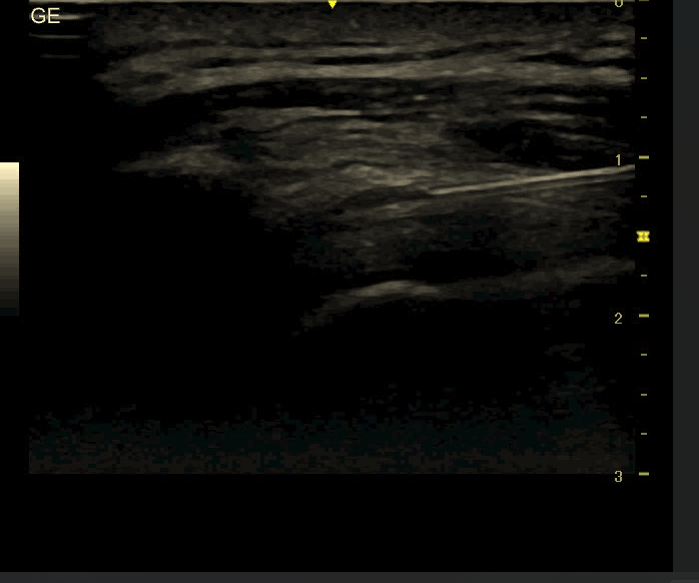

2. Precyzja ma znaczenie – szczególnie w trudnych lokalizacjach

Niektóre struktury anatomiczne są szczególnie trudne do „trafienia” bez kontroli obrazowej, np.:

- staw biodrowy,

- staw krzyżowo-biodrowy,

- pochewki ścięgien,

- okolice nerwów obwodowych,

- głęboko położone kaletki.

W takich przypadkach USG:

- pozwala dobrać optymalną drogę wkłucia,

- minimalizuje uraz tkanek,

- zwiększa skuteczność nawet przy mniejszej dawce leku.

To właśnie dlatego iniekcje pod USG są coraz częściej rekomendowane w wytycznych klinicznych, a nie traktowane jako opcja „dodatkowa”.